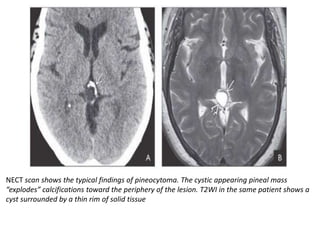

NECT scan shows the typical findings of pineocytoma. The cystic appearing pineal mass

“explodes” calcifications toward the periphery of the lesion. T2WI in the same patient shows a

cyst surrounded by a thin rim of solid tissue